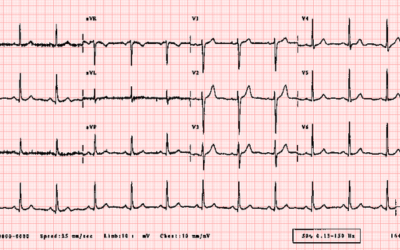

Ecg